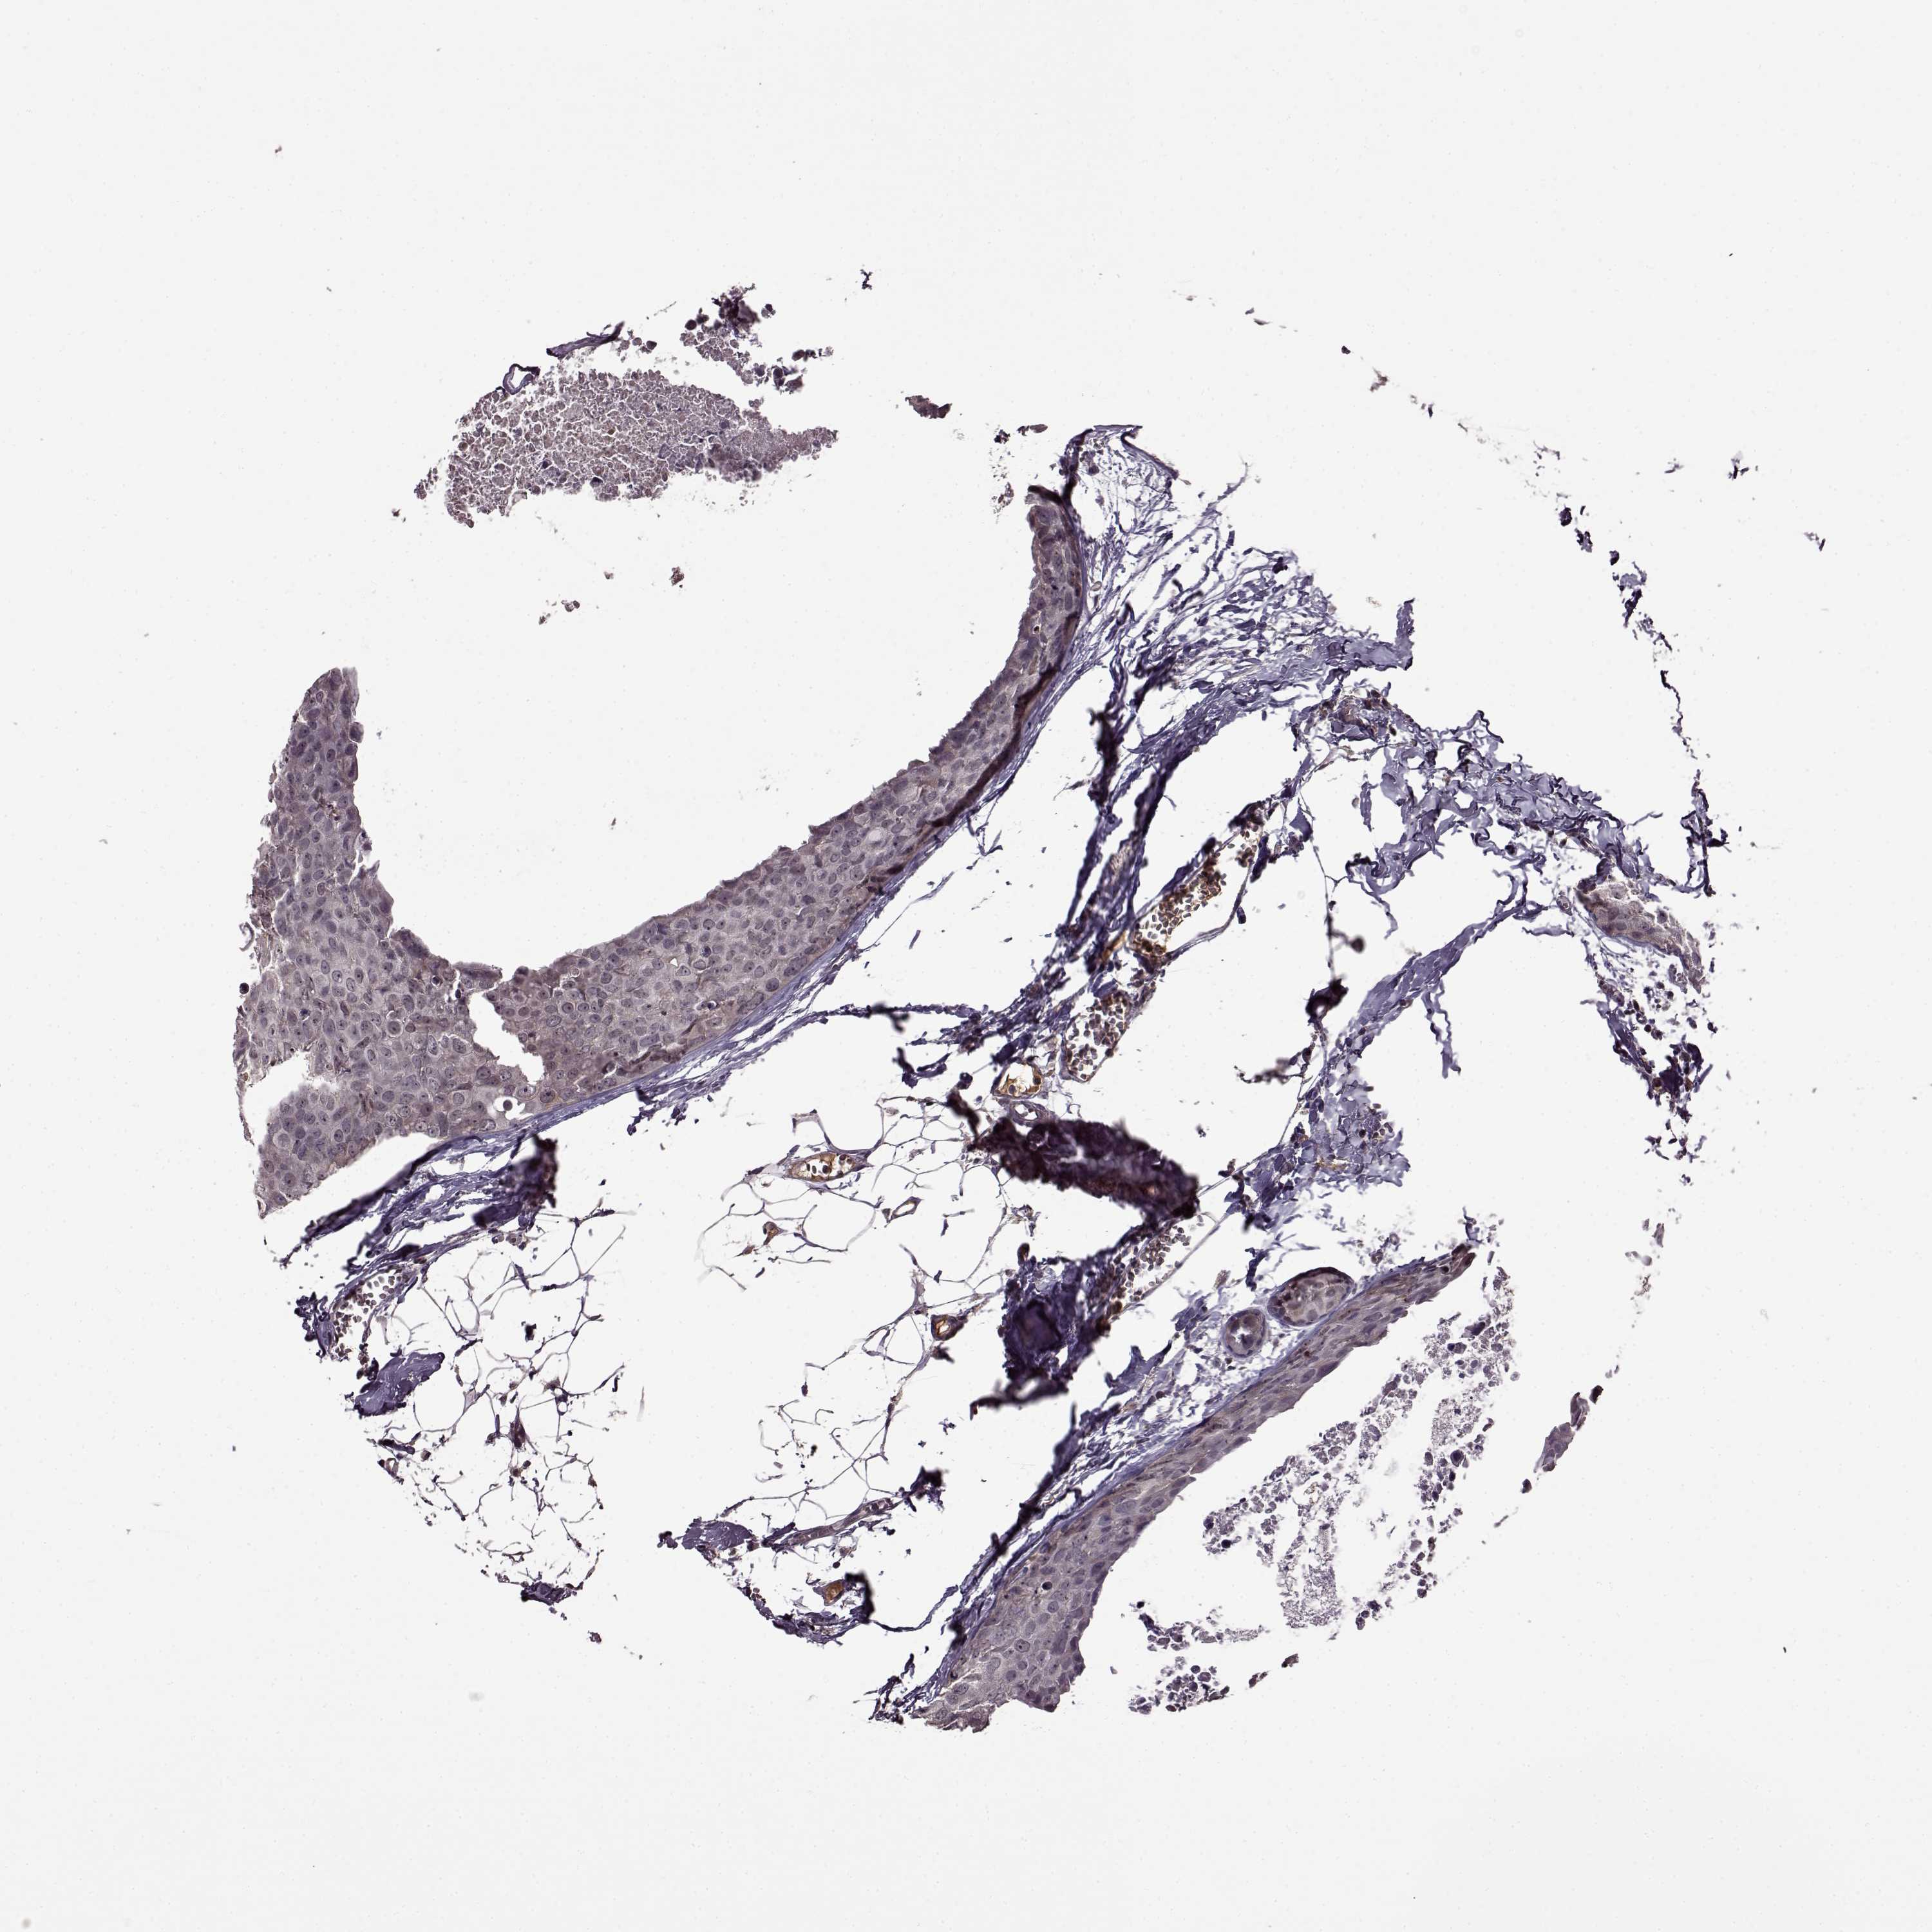

CANCER BREAST CANCER Show tissue menu

BRCA TCGA BRCA VALIDATION PROTEIN EXPRESSION